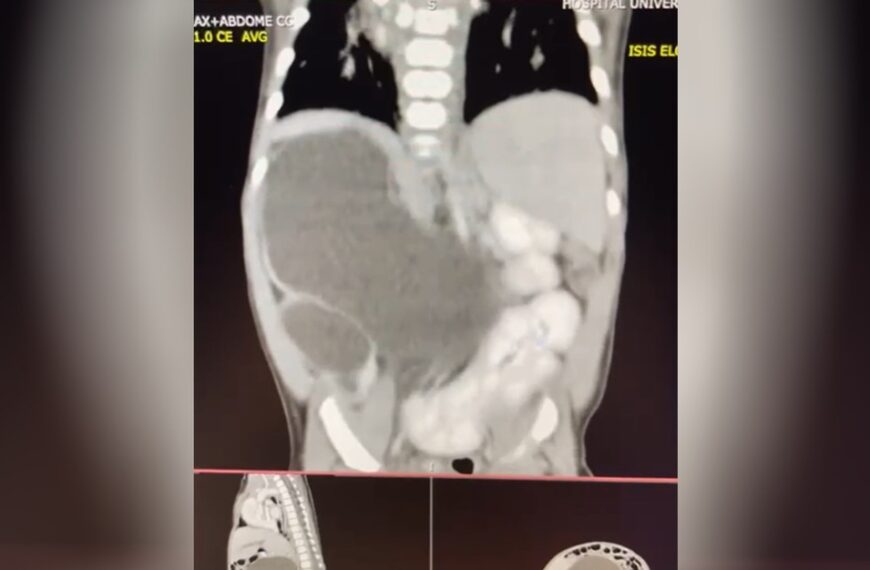

Imagem: Reprodução